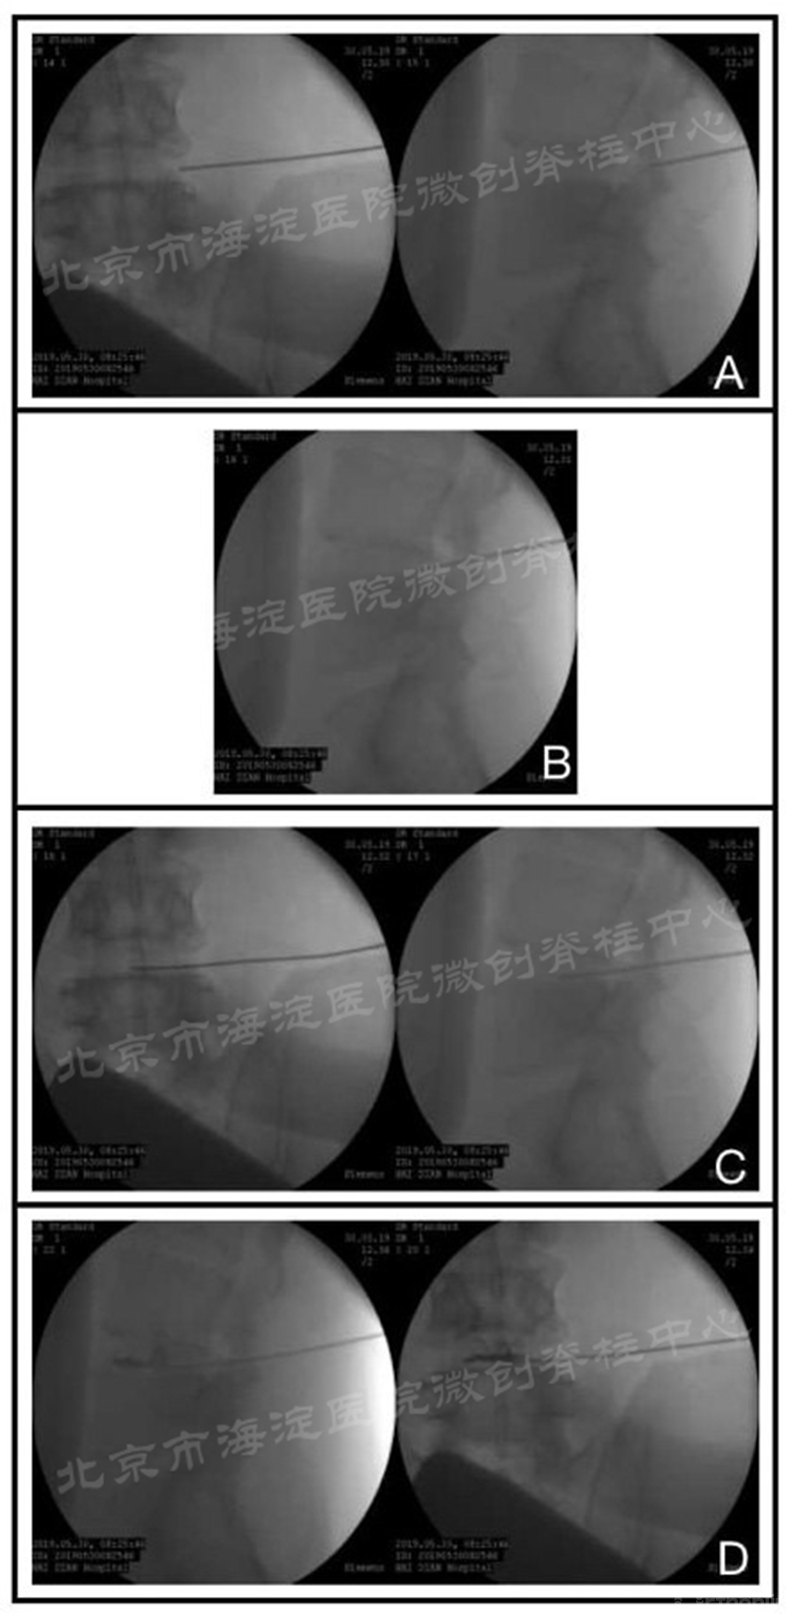

3.术中透视定位时机(图4):

①针尖到达上关节突上外侧面→正侧位透视(图4-A);

②旋转针尖,将斜面面向关节突表面向下滑行进针1cm后→侧位透视;

③出现皮革样感觉并成功突破后→侧位(图4-B);

④进针至椎体中心后→正侧位(图4-C);

⑤椎间盘造影→正侧位(图4-D)。

图4